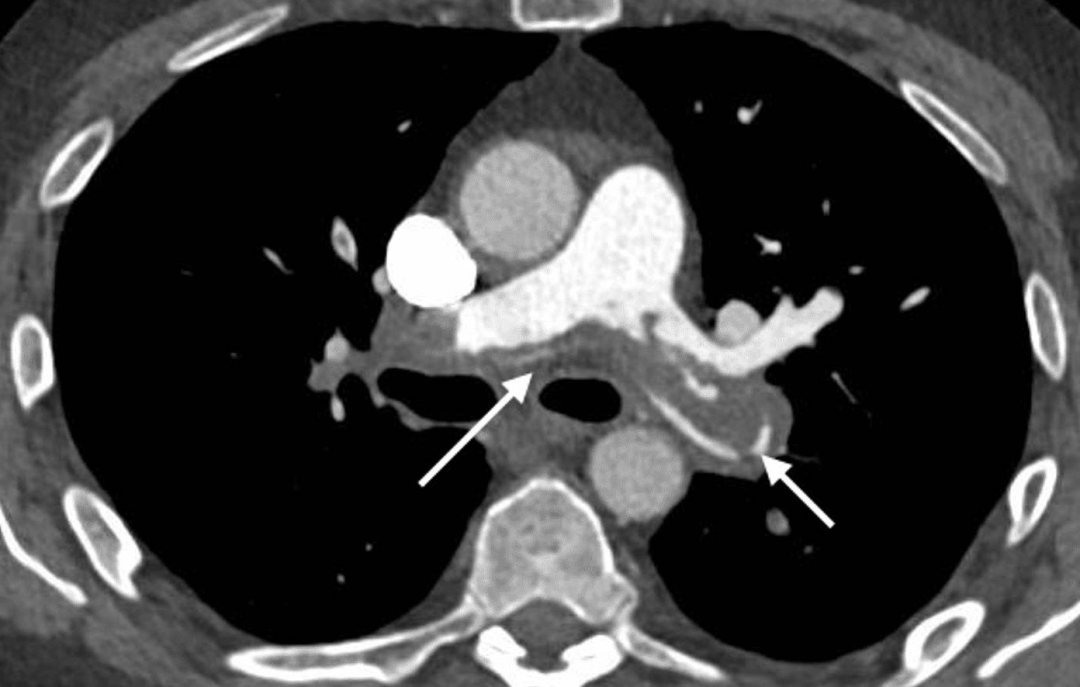

随后,检验结果显示:肌钙蛋白I:28.3 ng/L(参考范围:<2.5 ng/L),NT-pro BNP:13,151 ng/L(参考范围:<400 ng/L),D-二聚体:>20 µg/ml(参考范围:<0.5 ug/ml)。胸部X光未见异常,CT肺血管成像(CTPA)显示肺干内有鞍状血栓,延伸至主肺动脉和远端分支(图2)。

图2. CTPA显示肺干内鞍状血栓(白色箭头)